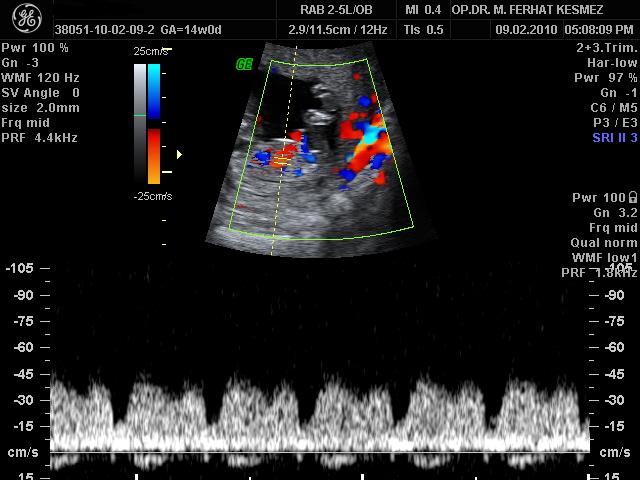

Ultrason Ölçümleri